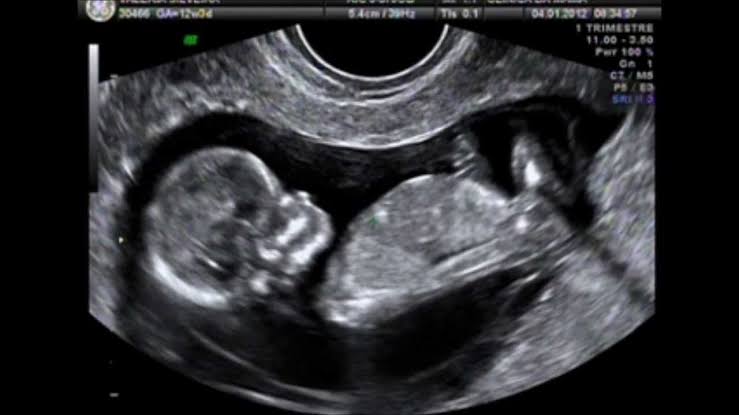

A decisão do ministro Alexandre de Moraes, do Supremo Tribunal Federal (STF), de derrubar resolução do Conselho Federal de Medicina (CFM) que impedia que médicos matassem bebês após 22 semanas de gestação, desagradou conservadores e parlamentares da bancada pró-vida no Congresso Nacional.

Relembre o caso

Em abril, o Conselho Federal de Medicina (CFM) publicou uma resolução proibindo a assistolia fetal a partir das 22 semanas de gravidez nos casos de estupro, situação em que o aborto não é punido no Brasil. Como apontou reportagem da Gazeta do Povo, a falta de rigor no controle das alegações de estupro, combinada com a interpretação de que não punir significa permitir o aborto em qualquer momento, vinha facilitando, na prática, a realização de abortos em qualquer fase da gestação.